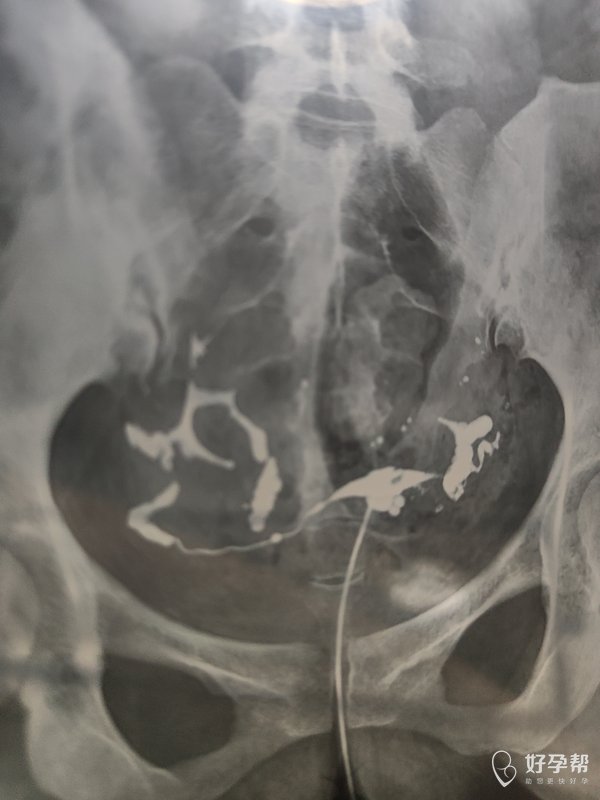

各位医生好前天做了输卵管造影请帮忙看看这些造

双侧输卵管通畅,弥散好,正常造影,可以试孕。